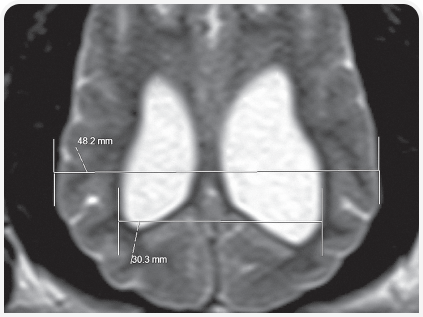

Диагноз ставится на основании изменения размера и формы черепа, неврологических признаков заболевания и нейровизуализации.